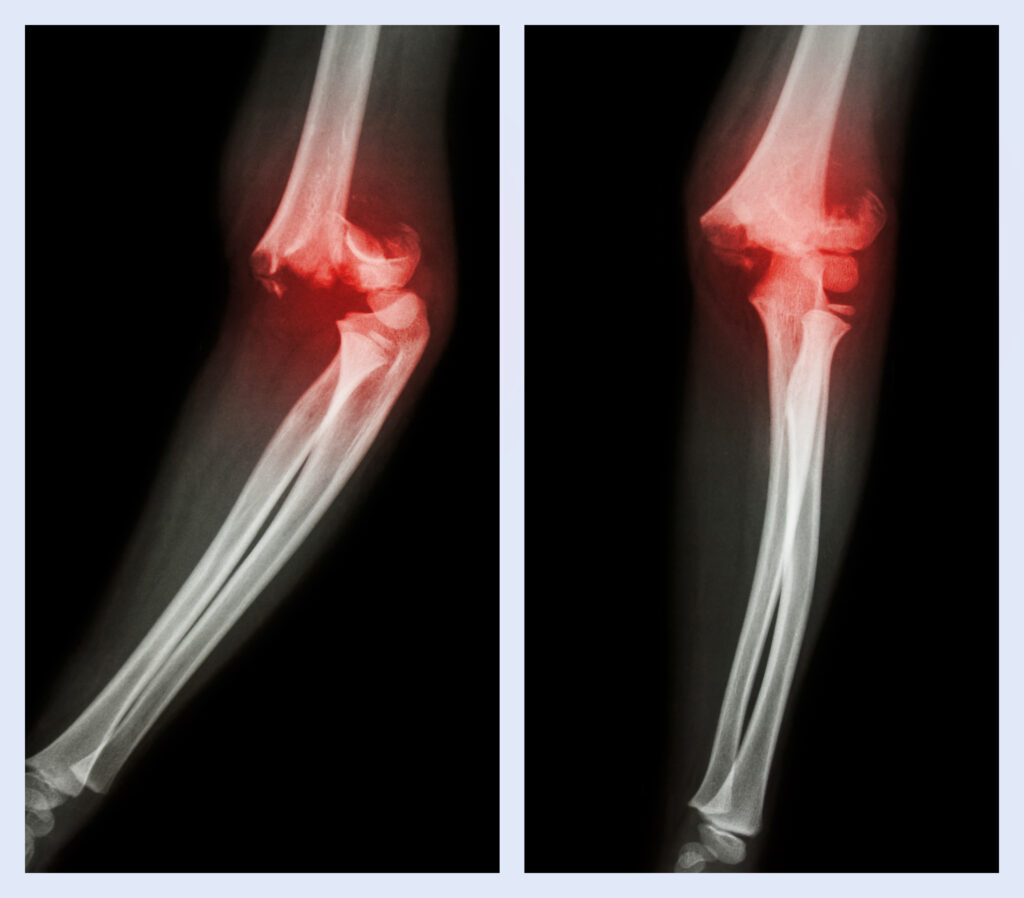

Elbow Dislocation

An elbow dislocation occurs when the bones of the forearm (radius and ulna) move out of their normal position in relation to the upper arm bone (humerus). It is one of the most common types of joint dislocations after the shoulder and can range from simple (without bone fracture) to complex (with associated fractures or ligament damage).

Visible deformity or abnormal positioning of the elbow